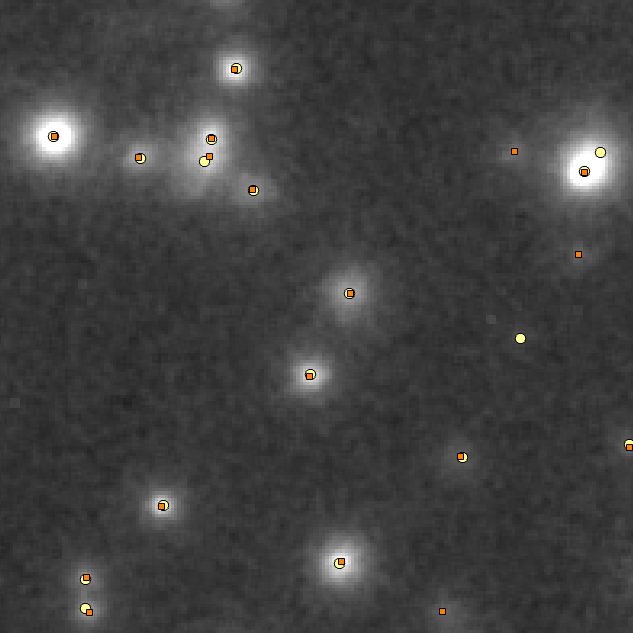

We used the algorithm in Fig. 2 with , , and the sequence proposed in [16]. The underlying parameters (see [7]) were set to . We run the algorithm for 10000 iterations, which were more than those needed for convergence. The resulting F1-Score was with precision and recall . On the left panel of Figure 3, we show a grayscale representation of the image under study, while on the right panel, we show both the detections proposed by the human expert (orange squares) and the ones proposed by our algorithm (yellow circles), on a specific section of the image.

In our opinion, both sets of detections are of comparable quality, with our algorithm being more precise in terms of cell locations and the human labeler obtaining higher recall for isolated cells. However, one has to take into account that the detections obtained by our algorithm have been thresholded to match the criteria of this specific expert, and thus, the absence of weaker spots in the set of detections can be explained by inconsistent inclusion criteria in the human labeling. A final relevant difference between the two sets of detections is that our algorithm uses the observation model to evaluate the whole shape of spots in terms of possible cells, instead of mainly relying on local luminosity. Hence, the algorithm includes detections that are weaker but fit the shape of cell-generated spots, as the apparent false positive in the middle-right region of the image. This also results in the correct decomposition of clusters of cells, as it is clearly the case of the large spot in the upper-right region of the image.